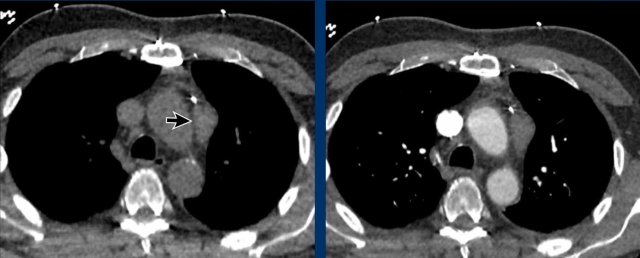

Case 1

These images are of a patient with a thymus carcinoma.

Notice the irregular activity in the periphery of the lesion on the PET.

The tumor was resected.

In the follow up a CT was made.

Continue with the follow up CT...

On the CT new hyperdense structures were seen in the vertebrae (arrows).

They were not there on a previous CT.

What is your opinion?

First study the images and then continue reading.

Images

Note the presence of dilated venous collaterals. This is explained by the fact that during surgery, the brachiocephalic vein is ligated, which can lead to the development of significant venous collaterals. The hyperdense structures observed in the vertebral bodies are not indicative of sclerotic metastases, but rather a consequence of venous congestion. These findings represent enhancement due to venous congestion, not metastatic disease. On a non-contrast CT, this hyperdensity would not be visible.

Continue with a later follow-up scan...

On a later follow up scan the venous congestion is not visible anymore.

Case 2

These images are of a 43-year-old male with chest pain.

There is a mass in the prevascular mediastinum.

The border is irregular and the lesion is positive on a PET-CT.

Discussion

The most likely diagnosis was a thymoma, probably invasive or even a carcinoma.

Continue with a preoperative scan two months later...

Two months later a preoperative scan was performed.

It is clear that the lesion is smaller.

However the surgeon decided to resect the lesion anyway and it turned out to be a thymus carcinoma.

We have no clear explanation for what happened here.

There is some reaction in the soft tissues surrounding the tumor on the first scan (arrow).

Maybe there was some inflammation within the tumor and surrounding tissues, which made the tumor look bigger.